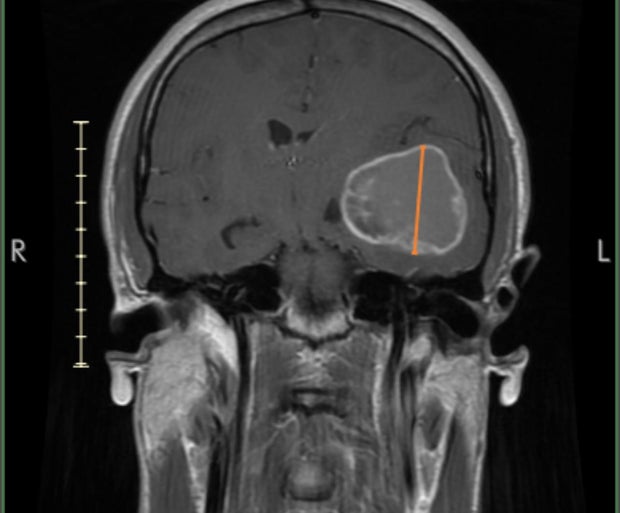

At just 28 years old, Bienvenu faced an uncertain future when surgeons rushed to remove a lemon-sized glioblastoma brain tumor, revealing it was stage 4. He thought that could be the end for him.

After the initial diagnosis, he underwent a major surgery to remove the tumor and the doctors believed they successfully removed all of it. Following the surgery, he underwent chemotherapy. There was a recurrence and he required another surgery to remove a portion of the recurrent tumor. To address the remaining tumor, he underwent gamma knife treatment, a form of radiation therapy and continued with several years of chemotherapy.